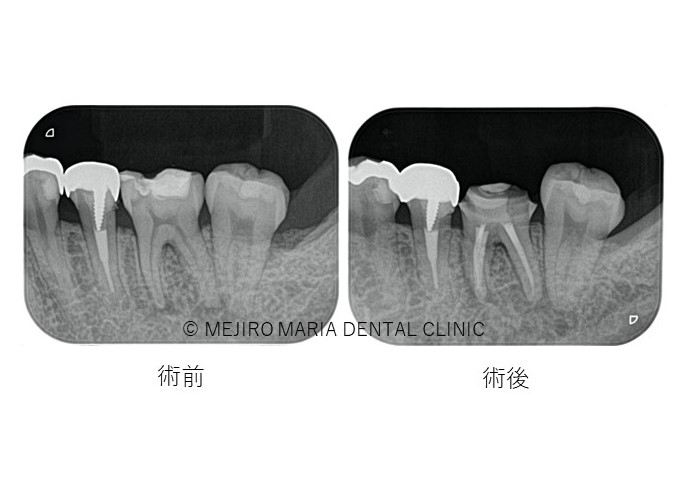

治療終了後、良好に根の中にバイオセラミックが充填され封鎖できていることを確認し(画像A)、3ヶ月後の経過観察にて、痛みや違和感がないことはもちろんのこと、術前、術後に確認できていた根尖性歯周炎の透過像の縮小を確認(画像B)し経過が良好であると判断しました。

|患者様利益を考えた精密根管治療_治療後_術前術後の比較レントゲン画像.jpg)

この患者様はお仕事の都合上、多くの回数を歯科医院に来院されることが難しい患者様でした。今回の治療も2回の来院で根管治療を終了し、3ヶ月後に経過観察を行い問題がないことを確認し治療を終了いたしました。合計で4回の来院で治療を完了しました。